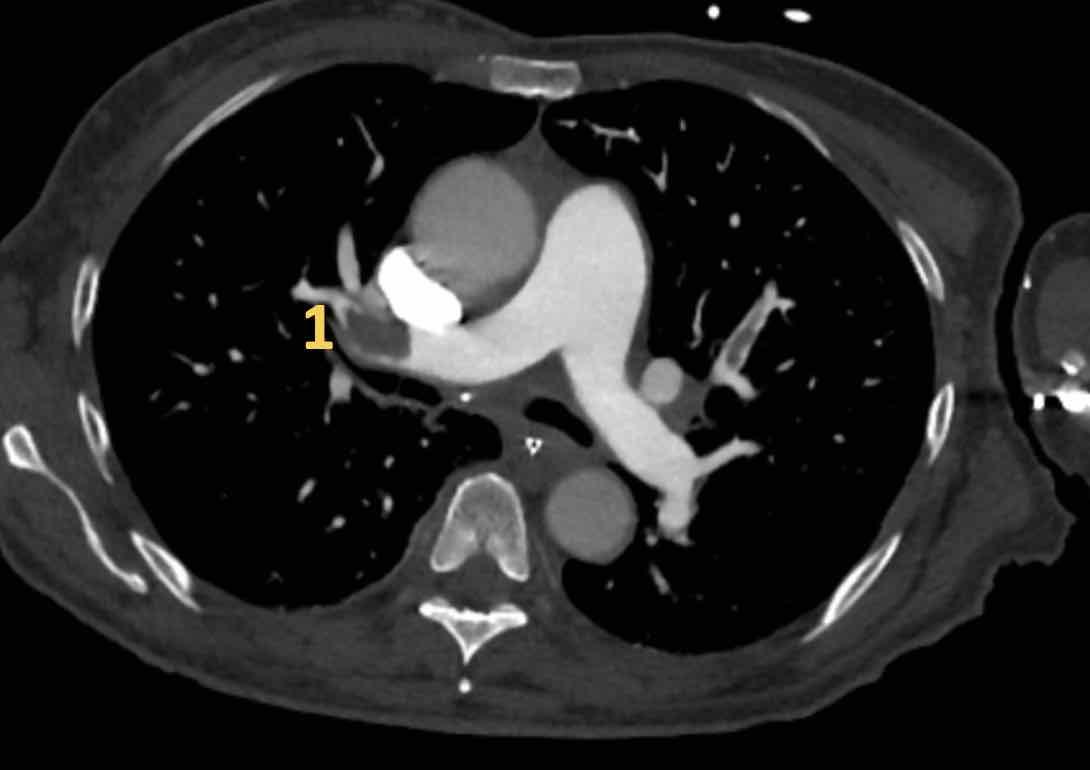

Hình ảnh

Đây là các hình ảnh của bệnh nhân nữ 59 tuổi tại khoa cấp cứu,

minh họa rõ ràng các huyết khối ở các mức độ khác nhau.

Cuộn qua các hình ảnh.

- Huyết khối trong động mạch thùy đến thùy trên phổi phải.

- Huyết khối tại lỗ vào của động mạch phân thùy đáy sau của thùy dưới phổi phải.

- Huyết khối dưới phân thùy ở phân thùy đáy trước của thùy dưới phổi phải, vài nhánh phía sau động mạch phân thùy.

- Huyết khối tại chỗ phân đôi phân thùy của thùy trên phổi trái.

- Huyết khối tiếp tục lan về phía ngoại vi trong động mạch dưới phân thùy.